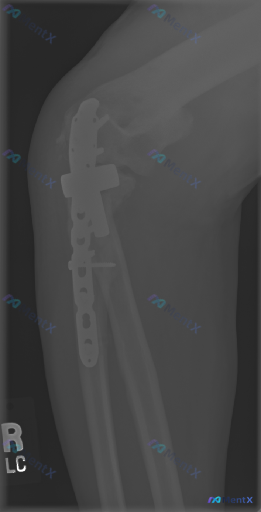

整理了一份左肘关节的病例资料,先抛出来大家一起看看。 基本背景: 左肱骨远端+尺骨鹰嘴骨折切开复位内固定术后,复查侧位X光。 影像报告给出的常规描述: - 肱骨远端双钢板、尺骨鹰嘴张力带钢丝+长螺钉固定,位置尚可 - 骨折对位可,关节关系维持,未见明显脱位/半脱位 - 未见明显内固定断裂、松动征象...

整理到一组左侧肘关节(标注为L)的侧位X光片影像资料,结合读片分析,核心发现如下: - 骨结构:尺骨近端(靠近肘关节处)可见骨皮质中断,有明显斜行骨折线伴移位、成角;肱骨远端干骺端也可见皮质中断;桡骨近端未见明确皮质中断。 - 关节关系:肘关节正常解剖结构破坏,肱骨、尺骨、桡骨之间的关节匹配关系明显...

整理到一份影像读片资料,觉得很适合讨论临床思维里的“小陷阱”。 先不说结论,只看原始情境:有人拿到这张影像,第一定位错了,后面的分析全偏了。再仔细看,还有个更大的问题——金属伪影把关键区域挡住了,看似“没明显异常”,其实什么都没法确定。 大家觉得: 1. 拿到这类带内固定的复查片,第一步最应该先确认...